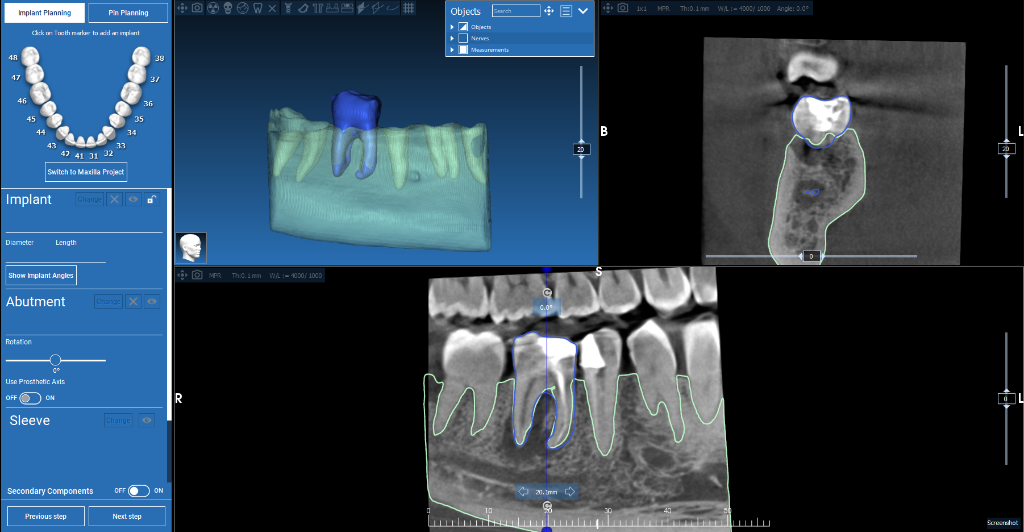

Surgical Guide Design Portfolio

Dental implant guides, apical resection & autotransplant cases from our practice

How Digital Implant Planning Works

From CBCT scan to 3D-printed surgical guide in 4 steps